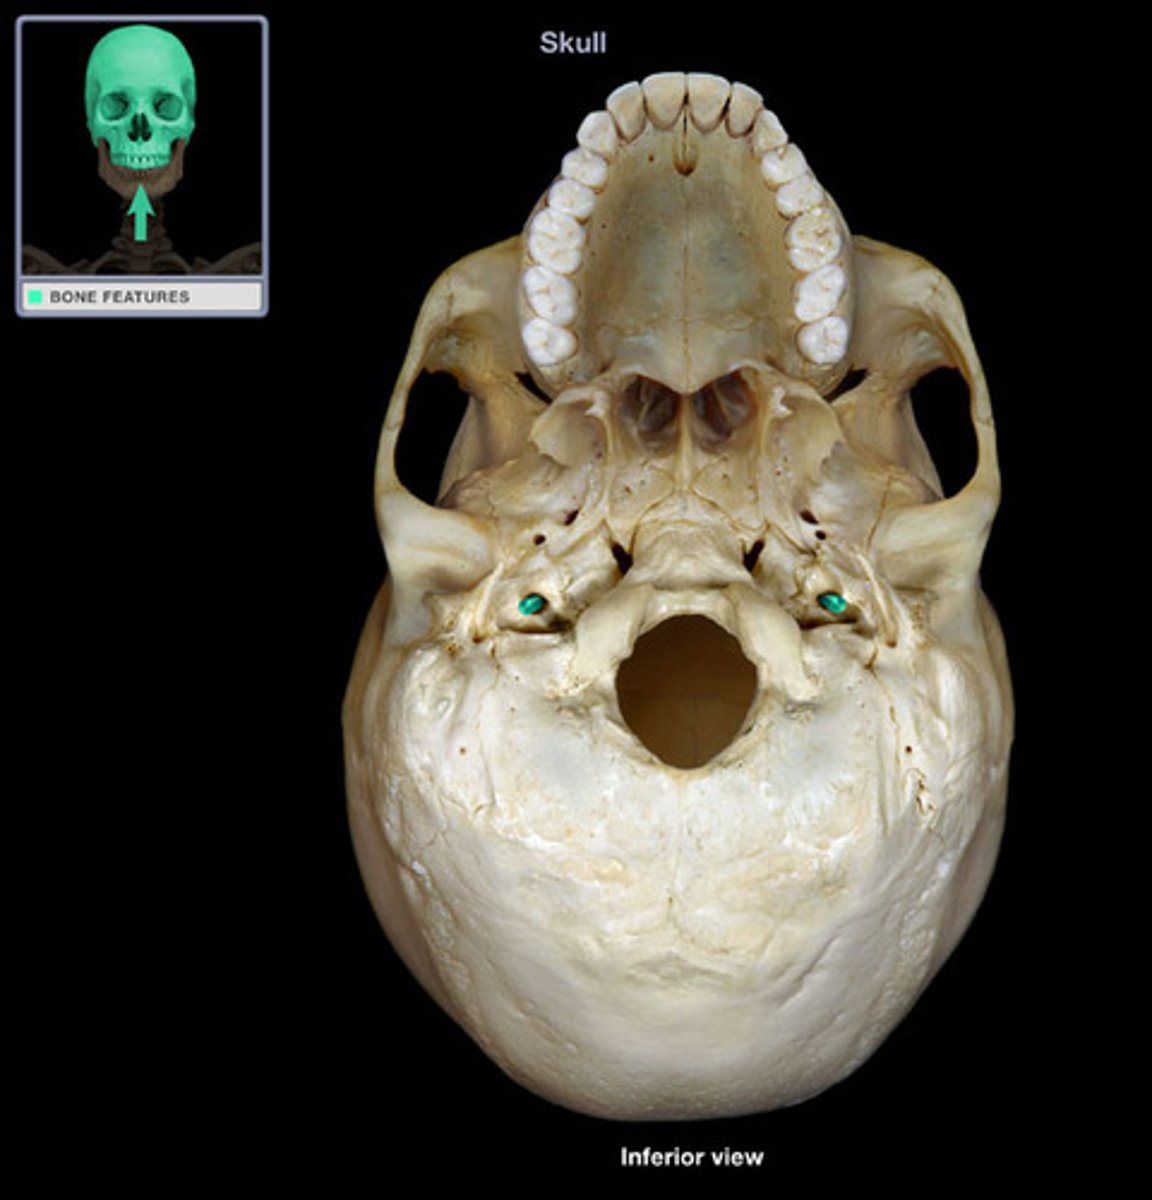

foramen magnum

occipital condyles

jugular foramen

hypoglossal canal inferior view

condylar fossa

mandibular fossa

foramen lacerum

carotid canal